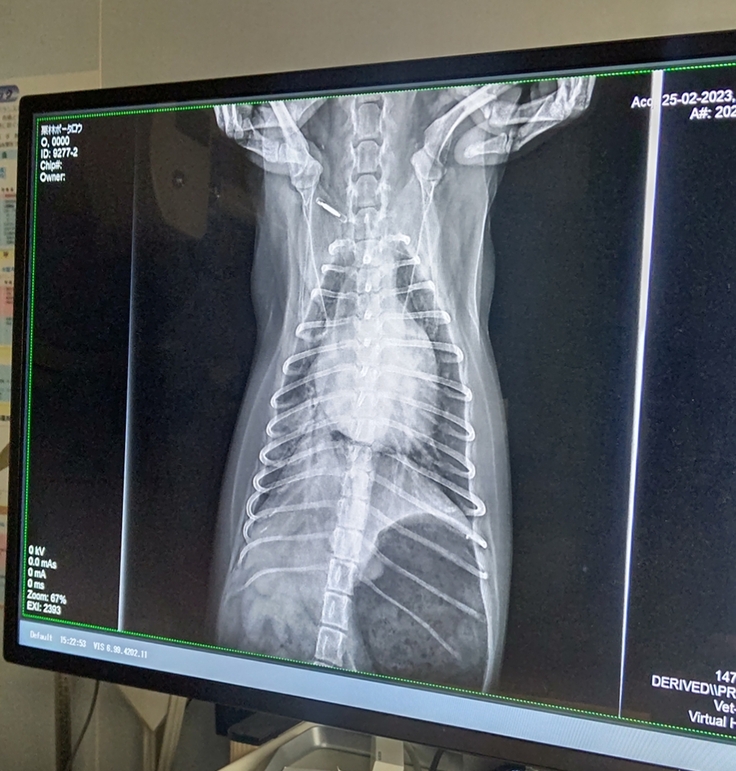

しかし、2023年2月25日、朝の薬も飲めず食事も食べられない状態で容体の 急な変化【意識なく倒れる】が見られた為、病院へ行きました。

診断の結果、肺水腫を発症していることが判明。

レントゲンを見せて頂き、肺下の一部分に水が溜まって白くなっており高濃度酸素吸入器に入り利尿薬を投与、4時間後、落ち着いた様でボー太郎と帰宅出来ました。